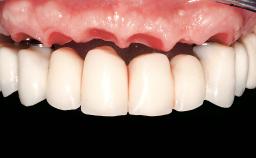

Immediate Loading of Six Implants in the Mandible and Six Implants in the Maxilla and Final Restoration with Full-Arch CAD/CAM Metal Framework FDPs Involving Digital Planning and Guided Surgery

Immediate loading of dental implants is increasingly popular with clinicians and patients. The idea of delivering a restoration directly after implant insertion,combined with a less invasive procedure (flapless protocol), has made treatment protocols involving dental implants more accessible to dentists and patients. However,immediate-loading concepts require sophisticated and exact planning. To facilitate this, conventional panoramic tomographs and periapical radiographs are often taken with the patient wearing a radiographic template simulating the preoperative prosthetic design. However, these radiographs do not provide all the necessary information. In addition, some protocols call for conventional surgical templates fabricated on the diagnostic cast. These will inform the bone drilling points and drill angles, but do not reference the underlying anatomical structures or provide exact 3-D guidance.

Defining Characteristics Fully edentulous upper jaw to be rehabilitated with four or more implants

Modality 6+ implants with immediate loading

SAC Level Complex

Defining Characteristics Fully edentulous upper jaw to be rehabilitated with an implant-borne fixed dental prosthesis

Loading Protocol Immediate

Retention Screw-retained, with 4 or more splinted implants Screw-retained, with 4 or more splinted implants